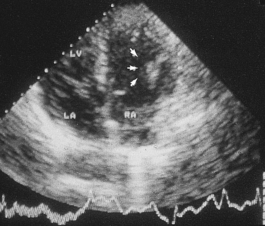

In life, cardiac structure can be assessed by a variety of invasive and non-invasive techniques. Chest X-rays provide a general guide to cardiac and aortic size. Echocardiography, coupled with Doppler techniques, gives a detailed view of individual chambers and in particular the contractile function of the ventricular cavities, the appearances of the individual valves and the direction of blood flow through them. More detailed images are obtained by passing a transducer into the oesophagus or stomach—trans-oesophageal echocardiography. At present the detailed anatomy of the coronary artery tree can be analysed only by injecting radio-opaque contrast medium into the coronary arterial orifices—coronary arteriography. Computed tomography (CT) and nuclear magnetic resonance imaging (MRI) are increasingly used by cardiac radiologists and can provide detailed images of individual chambers and the aortic lumen and wall.

HEART FAILURE

Chronic heart failure is a common condition with a poor prognosis. It is associated with disabling symptoms such as fatigue, poor exercise tolerance and shortness of breath on light exercise. Patients with established heart failure have median survival rates of about 3 years, less than in many forms of cancer. The clinical diagnosis of early, compensated heart failure is very difficult. There is no simple laboratory test that identifies patients with heart failure, and echocardiography is required for accurate diagnosis. Heart failure is the end result of many different forms of heart disease. Wherever possible the underlying causes of heart failure should be identified early in the course of a patient’s illness.